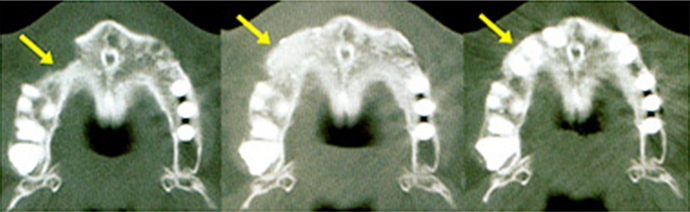

マイクロスコープ下での治療には、長い治療時間はもちろんのこと、高い治療技術が求められます。しかしそれがないと、特に根管治療(根の治療)の際に、根尖孔そのものや、根尖での分岐、側枝はもちろん、根管の微細な構造を発見し、その内部を見ながら治療を行うことは、ほとんど不可能となります。また細菌はそういった部分に潜んでいることが多いため、再発の原因となってしまうこともあります。

したがってマイクロスコープの導入は、当クリニックの再発の少ない最善の治療を提供するという理念のためには、欠くことのできないものであると思っています。